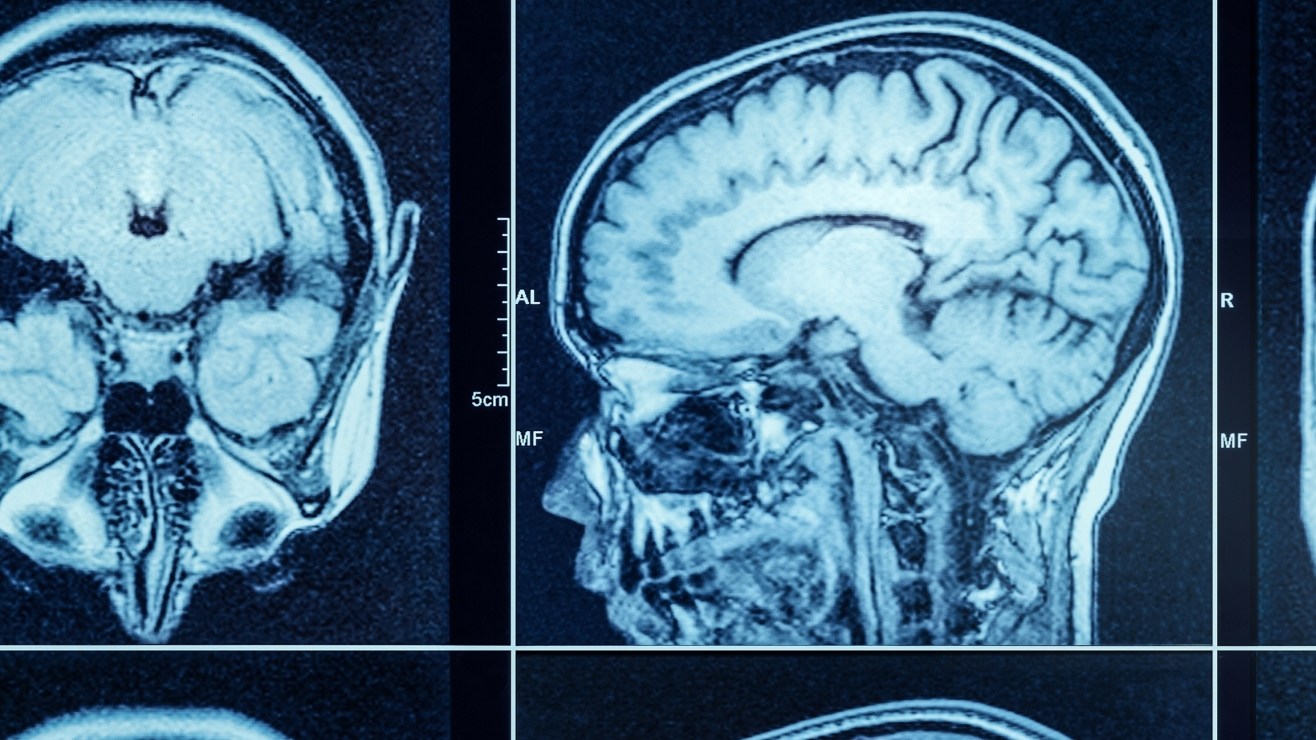

Tomografía computarizada de un cerebro. Crédito: Triff | Shutterstock

Una investigación reciente ha demostrado que el cerebro de los hombres se encoge más rápidamente que el de las mujeres a medida que envejecen. Sin embargo, las mujeres tienen una tasa de diagnóstico de Alzheimer casi el doble que los hombres.

Este descubrimiento, publicado en las Actas de la Academia Nacional de Ciencias (PNAS), se basa en el análisis de más de 12,000 exploraciones cerebrales.

Los investigadores, encabezados por Anne Ravndal de la Universidad de Oslo, observaron a cerca de 5,000 personas sanas, con edades entre 17 y 95 años, y cada participante fue sometido a un mínimo de dos resonancias magnéticas, lo que permitió a los científicos evaluar las variaciones en la estructura cerebral a lo largo del tiempo.